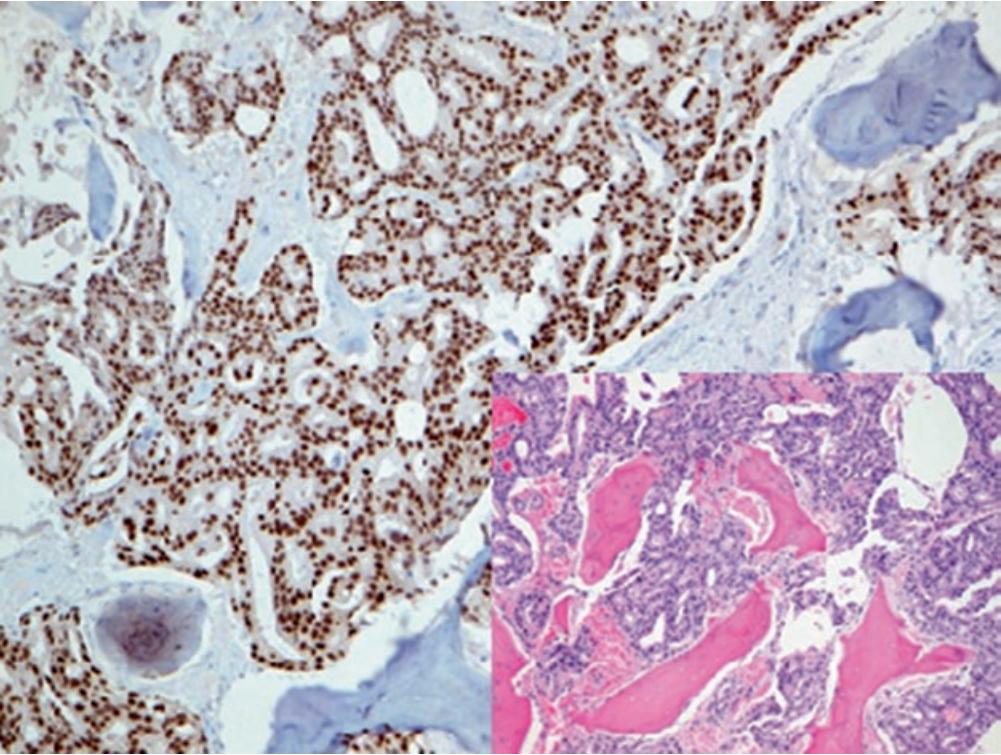

AMACR也称p504S,其功能与支链脂肪酸代谢、胆酸合成有关,表达于多种正常及肿瘤性细胞的线粒体及过氧化物酶体。相比良性前列腺腺体来说,前列腺癌的时候AMACR过表达。

图1. 前列腺腺癌,腔面细胞表达AMACR。

现在,该指标与p63联合,广泛用于前列腺癌的诊断;其中p63用于肌上皮标记,且为细胞核着色。具体来说,这一双染做法的结果可具体归为下述三种情况之一:AMACR阳性前列腺腺体,缺失p63阳性的肌上皮,这是肿瘤性腺体的特征;AMACR阳性前列腺腺体,周围有p63阳性的肌上皮,这是前列腺高级别PIN的特征;AMACR阴性前列腺腺体,周围有p63阳性的肌上皮,这是正常前列腺的特征。AMACR的表达,还可见于多种其他肿瘤,因此实际工作中应注意,该指标并非前列腺肿瘤所特有。P63免疫组化检测中,可用低分子量CK(如CK5&6、CK14)来代替。